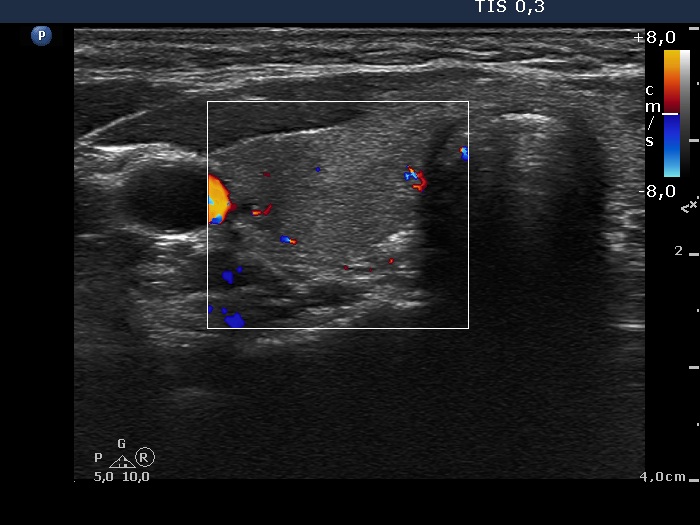

Follow-up 2 months after the first visit (3rd row of images):

Clinical presentation: Within 24 hours of the administration of 32 mg methylprednisolone, the neck complaints and subfebrility had stopped. When the patient reduced the dose to 8 mg daily for 2 weeks as suggested, the left lobe became sensitive. This tenderness has now been significantly reduced, but still persisted at times.

Palpation: The left lobe was tender on palpation.

Laboratory tests: TSH 1.62 mIU/L, FT4 9.97 pM/L, CRP 0.1 mg/L.

Ultrasonography: The right lobe decreased in size as did the extent of hypoechogenic areas in this lobe. The left lobe remained unchanged.

Suggestion: Discontinuation of steroid therapy. TSH in three months.